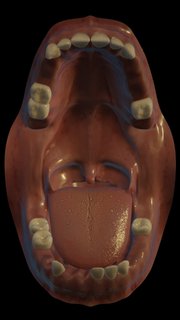

| 08:49, 1. Sep. 2024 | Kennedy vollbezahnt ohne 8er.png (Datei) |  |

1,5 MB | Len | Datei hochgeladen mit MsUpload | 1 |